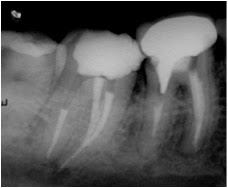

Introduction: Root canal irrigation carries a risk of extrusion of irrigant into the periapical tissues. The objective of this study was to compare different irrigation systems in matched pairs of teeth prepared to an apical size of 35.06 and 50.06 by measuring the frequency and extent of apical extrusion of sodium hypochlorite (NaOCl) into a simulated periapical environment. The null hypothesis was tested that there is no difference between systems.

Methods: Bilaterally matched pairs (n = 10) of single-canal extracted human anterior teeth were instrumented to an apical size of either 35.06 or 50.06. Teeth were embedded in a gel containing the pH-sensitive dye M-cresol purple that changes from yellow at pH 7.4 to purple at pH 9. Root canals were irrigated with 6% NaOCl (pH 11) by using EndoActivator (EA), EndoVac (EV), Rispi- Sonic/MicroMega 1500 (MM), passive ultrasonic irriga- tion (PUI), and syringe irrigation with a slot-tipped needle (SN), so that each tooth underwent all irrigation procedures in a randomized crossover design. Apical extrusion was evaluated by image analyses.

Results: The frequency of extrusion was less in teeth with apical preparation size 35.06 (36%) compared with 50.06 (60%) (P = .014) and was dependent on the irrigation system in 35.06 (P = .039) but not 50.06 groups. In the 35.06 group the frequency of extrusion was less for EV than for MM and SN (both P = .029). The extent of extrusion was less for MM compared with PUI (P = .024) and SN (P = .046) in the 35.06 group and greater for SN compared with all other systems in the 50.06 group (P < .05). The null hypothesis was rejected.

Conclusions: The frequency of apical extrusion of NaOCl was dependent on the type of root canal irrigation system and apical preparation size. The extent of extrusion depended on the irrigation system, with syringe and slotted-needle irrigation resulting in the greatest extent of extrusion.